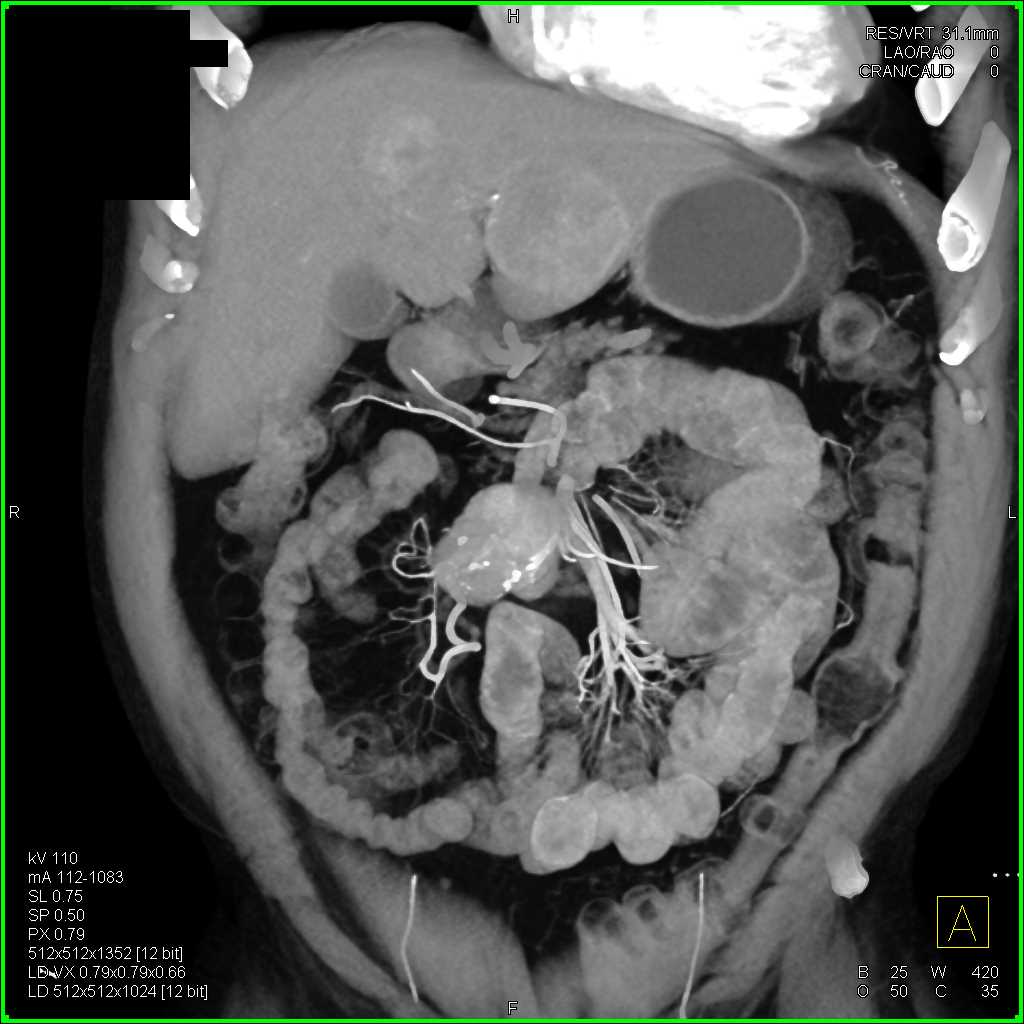

Carcinoid Tumor with Desmoplastic Reaction